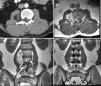

Los ganglioneuromas lipomatosos son una variante poco frecuente de los ganglioneuromas, que se caracterizan por presentar un componente adipocítico maduro entremezclado con un componente convencional de ganglioneuroma. Presentamos el caso de un paciente de 34 años con una lesión paravertebral L1-L4 derecha con extensión intraespinal y con déficit neurológico secundario, que fue intervenido en nuestro centro. La anatomía patológica confirmó la presencia de una neoplasia encapsulada amarillenta, que al microscopio presentaba áreas de ganglioneuroma mezcladas con áreas de grasa madura.

Lipomatous ganglioneuromas are a rare variant of ganglioneuromas characterized by a mature adipocytic component admixed with a conventional ganglioneuroma component. We present the case of a 34 year old patient with a paravertebral right lesion L1-L4 with intraspinal extension and secondary neurological deficit, who underwent surgery in our hospital. The pathological anatomy showed a yellowish encapsulated neoplasm, which under microscopic evaluation showed areas of ganglioneuroma admixed with areas of mature fat.